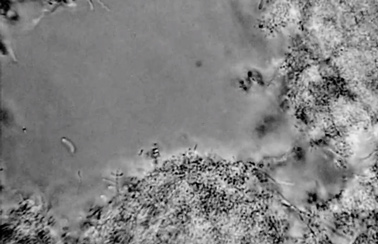

Microscopic pre- and post-treatment images of plaque from a periodontal pocket treated with AgNPs are shown in Figure 2 and Figure 3.

Fig 2. Pre- (Fig 2) and post-treatment (Fig 3) microscopic images of periodontal pocket plaque treated with plant-based silver nanoparticles. In a comparison of the two images, a notable reduction of pathogenic motile bacteria can be visualized in the sample after AgNP application (Fig 3).

Figure 2